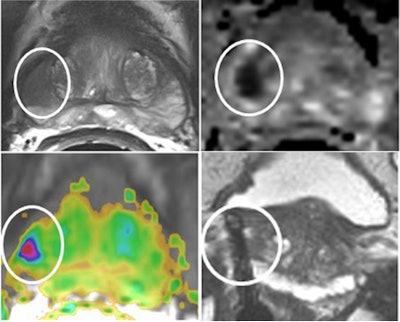

A 69-year-old patient with a low-grade (Gleason 3+3) prostate cancer (1/10 cores positive, < 5%) confirmed by transrectal ultrasound biopsy. Therefore, the patient was a candidate for active surveillance. Top left: T2-weighted MRI shows low-signal lesion (circle) in right peripheral zone. Top right: ADC map shows restriction is this area (ADC value: 650), and bright area on high b value (1400) diffusion-weighted image. Bottom left: Dynamic contrast-enhanced MRI shows focal unilateral area with curve type 3. Prostate imaging reporting and data system (PI-RADS) classification for significant cancer: 5-5-5, final score 5. This fits an aggressive tumor. Bottom right: MR-guided biopsy shows lesion (circle); needle = white line, showed 2/2 cores each 80% Gleason 4+3 prostate cancer. Due to this MRI examination, this patient's prospects have improved, and he will now have a prostatectomy. Images courtesy of Dr. Jelle Barentsz, PhD.